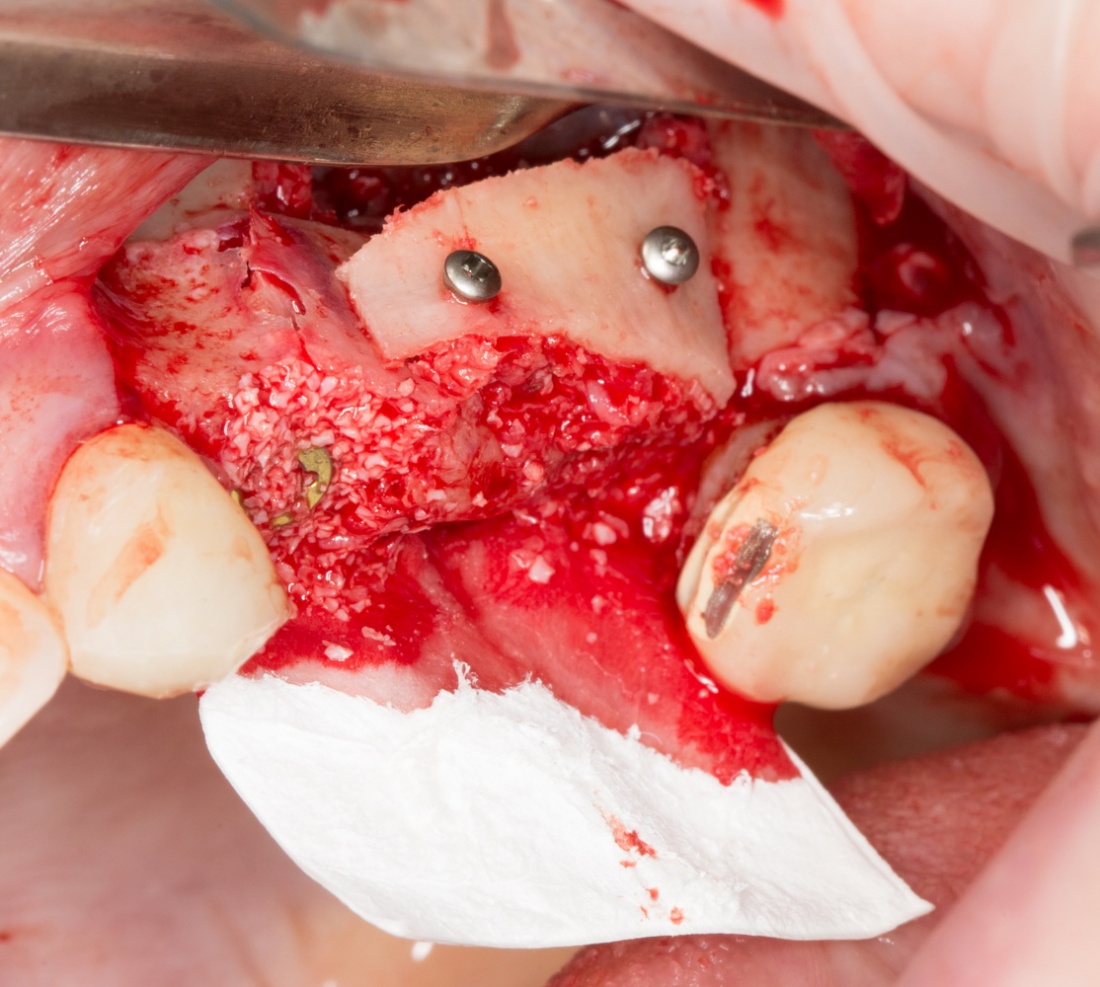

Остеопластика или «наращивание костной ткани» при имплантации — выбор метода и отдаленные результаты.